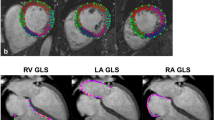

CMR postprocessing and analysis

Native T1 and T2 maps were calculated offline pixel-by-pixel from a set of images with different T1- and T2-weighting by two observers (BP and BV) experienced in CMR using in-house Mevislab tool (Vs 2.5.1 MeVis Medical Solutions AG, Bremen, Germany) and commercially available software package (suiteHEART®, Version 4.0.6, Neosoft, Pewaukee, Wisconsin, USA). Both readers were blinded to the scan (rest and post-exercise CMR), and clinical and biological data. Maps and error maps were calculated applying a validated retrospective motion correction method of the T1-weighted images (Tilborghs et al. 2019). A freehand region of interest (ROI) was drawn in the septum for global assessment using a fixed color code and range (lut royal; 650–1650 ms (ms) for T1 mapping, 0–80 ms for T2 mapping) and error maps to avoid evident susceptibility artifacts or adjacent blood pool and extra-myocardial tissue pixels (supplemental Fig. 1) (Schulz-Menger et al. 2020).

T1/T2 mapping

One cyclist was excluded because of non-diagnostic T1/T2 mapping image quality due to ECG-gating problems. Myocardial T1 relaxation times increased significantly post-exercise (1133 ± 48 to 1182 ± 46 ms, p < 0.001) in the 17 finishers (Fig. 3a and supplemental Fig. 2), while no significant change in T2 mapping (43.9 ± 2.8 to 44.1 ± 2.5 ms, p = 0.474) (Fig. 3b) was observed at SA maps (Table 3). Interobserver reproducibility (ICC, single measures) of blinded native T1 and T2 mapping measurements was excellent: T1: 0.985, 95% confidence interval (CI) 0.972 to 0.992; T2: 0.956, 95% CI 0.919–0.976. Bland–Altman plots with 95% limits of agreement confirmed the close agreement of both observers (supplemental Fig. 3a, b).